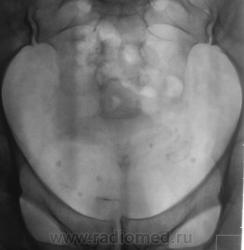

После введения контрастного вещества урограммы произведены на 7 и 15 минутах.

Да, контраст "покрыл" тень рентгеноположительного конкремента.

А мне этот конкремент, при всей его "рентгеноположительности", видится дефектом наполнения чашки, контрастированной ещё более "рентгеноположительным" контрастом)).

Ещё более отчетливо это может было бы увидеть на прицельной рентгенограмме почки либо томограмме её.